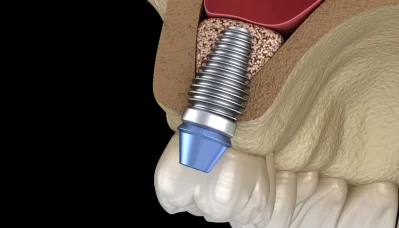

人工歯根療法とも言われ、歯を支える顎骨部分にボルトを埋め込み、人工の歯を被せる治療方法です。メリットとしては、ご自身の歯と同じような感覚で噛めるようになることが挙げられます。審美性が高いため、美しく仕上がることもインプラントの特長です。留意点としては、治療期間が長く、保険適用外のため治療費は高額になります。

インプラントを固定するためには、十分な量・厚みの顎骨が必要です。加齢や歯がない期間が長く続くなどの要因で顎骨が減っている場合、インプラントを埋め込む前に骨を作る手術を行います。

埋入手術

治療計画に従い、インプラントを顎骨に埋める手術を行います。骨造成が必要な場合、まずは骨を作ってインプラントを埋め込む2回法を取ります。

インプラントと顎骨が結合しましたら、アバットメントや人工歯を装着します。人工歯は患者様の口腔内に合うように、機能面や審美面にこだわって作製いたします。